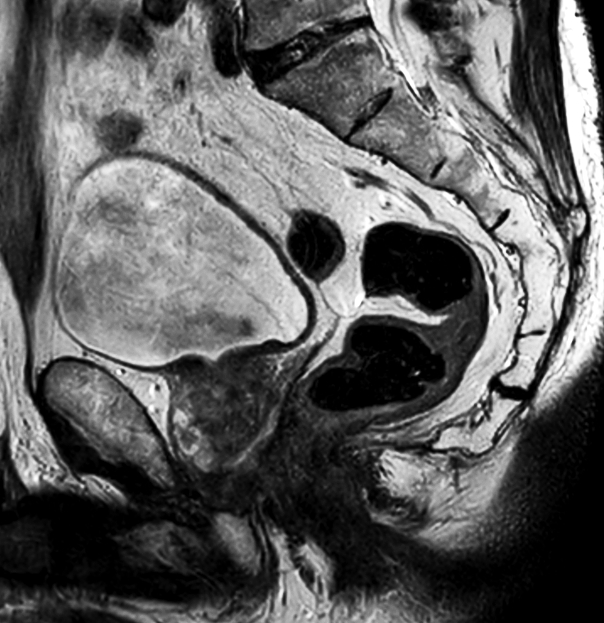

70-year-old male with prostate cancer, cT3bNxM, Gleason 6, PSA 7.9 mg/L, underwent MRI on Ingenia 3.0T MR-RT before radiation therapy, next to CT simulation. Patient was imaged at Ingenia MR-RT 3.0T using FlexCoverage Anterior Coil in combination with the integrated Posterior Coil.